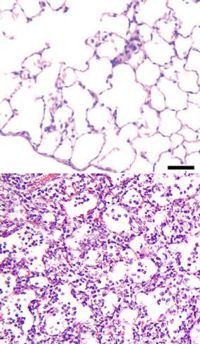

Viruses

Viruses invade cells in order to reproduce. Typically, a virus reaches the lungs when airborne droplets are inhaled through the mouth and nose. Once in the lungs, the virus invades the cells lining the airways and alveoli. This invasion often leads to cell death, either when the virus directly kills the cells, or through a type of cell controlled self-destruction called apoptosis. When the immune system responds to the viral infection, even more lung damage occurs. White blood cells, mainly lymphocytes, activate certain chemical cytokines which allow fluid to leak into the alveoli. This combination of cell destruction and fluid-filled alveoli interrupts the normal transportation of oxygen into the bloodstream.

Bacteria typically enter the lung when airborne droplets are inhaled, but can also reach the lung through the bloodstream when there is an infection in another part of the body. Many bacteria live in parts of the upper respiratory tract, such as the nose, mouth and sinuses, and can easily be inhaled into the alveoli. Once inside, bacteria may invade the spaces between cells and between alveoli through connecting pores. This invasion triggers the immune system to send neutrophils, a type of defensive white blood cell, to the lungs. The neutrophils engulf and kill the offending organisms, and also release cytokines, causing a general activation of the immune system. This leads to the fever, chills, and fatigue common in bacterial and fungal pneumonia. The neutrophils, bacteria, and fluid from surrounding blood vessels fill the alveoli and interrupt normal oxygen transportation.